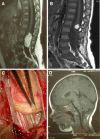

The surgical results of this series of occult spina bifida seem better than the natural history registered in the long pre-operative period in terms of neurological deterioration. The major contribution to this result is attributed to neurophysiological monitoring that lowers the risks of permanent damage and increases the percentage of effective detethering. The present series of TCS, due to conus and filar lipoma, documents that CM1 is a really rare association occurring in less than 6% of the patients, despite the low position of conus. The detethering procedure did not influence the tonsillar position, thus excluding the correlation between the tethering and the tonsillar descent. The genetic alteration documented in a girl reinforces the hypothesis of a rare complex polymaformative picture deserving multiple procedures according to the prevailing clinical symptoms.